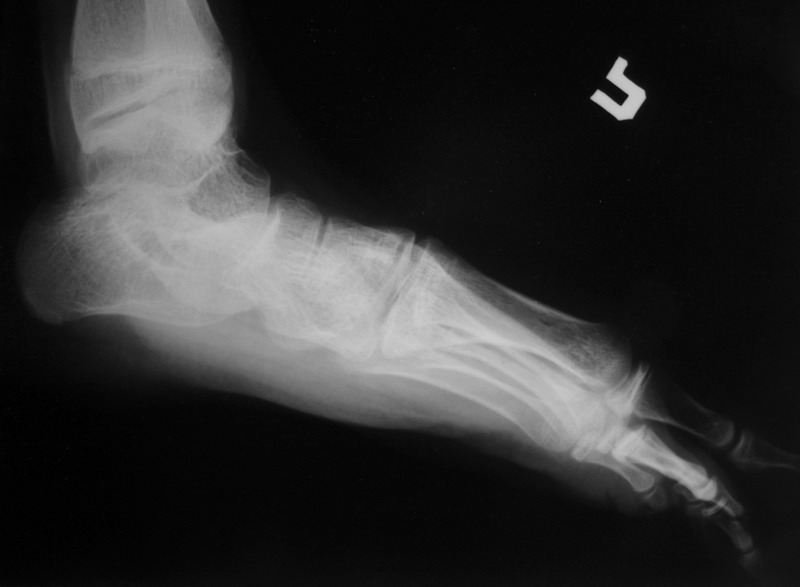

Пациент 15 л., болезнь Литтля, спастический нижний парапарез, интеллект высокий. Ребенок настроен на активный образ жизни. С недавнего времени начал ходить без дополнительной опоры. Появилась проблема с левой стопой - во время ходьбы опора приходится на смещенную кнутри таранную кость.

Может образоваться болезненный натоптыш или язва. Общепринятой операцией является трехсуставной артроде с мобилизацией таранной кости. Выполнять такую операцию у спастика и в раннем возрасте проблематично. Родстьвенники тем более готовы материально и морально осуществить хирургическое лечение за рубежом, если оно показано и возможно. Предпочтительно в Австрии и Германии. Если кто-то посоветует координаты таких клиник - были бы признательны.